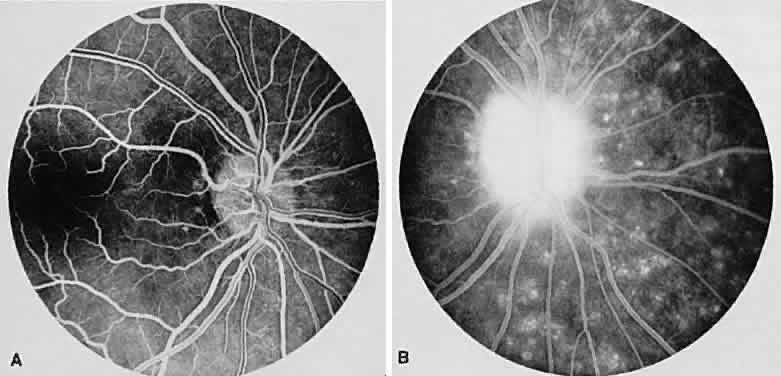

The FA reflects the various clinical entities. Retinal venular walls stain, particularly where there are perivenular exudates.25–27 More extensive venous involvement can produce a picture of dilated veins and perivenous leakage.27 Peripheral neovascularization occurs near areas of retinal capillary nonperfusion.25,28 Optic disc granulomas and optic disc neovascularization both leak extensively (Fig. 8A); sarcoid retinal lesions also stain (see Fig. 7B).27 In disc edema, the disc is hyperfluorescent and leaks fluorescein (see Fig. 8B).25

Fig. 8. Sarcoidosis. A. Fluorescein angiography shows two separate areas of neovascularization of the peripheral retina. B. Extreme leakage of dye from the right disc with cystoid macular edema of the right macular region in a patient with chronic sarcoidosis.